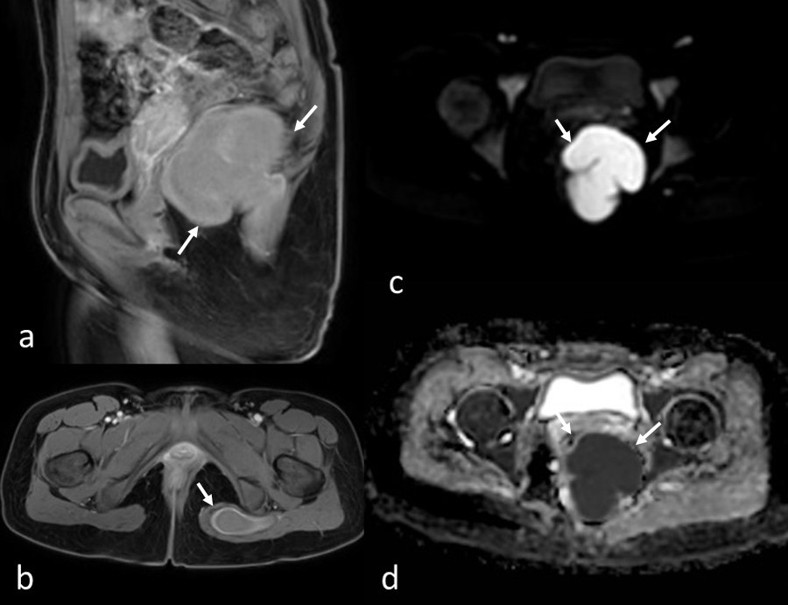

A suprapubic pelvic ultrasound revealed a septated cystic lesion measuring 7.5 x 6.5 cm, located posterior to the uterus and left ovary. The uterus and ovaries appeared normal in size and morphology. Magnetic resonance imaging (MRI) demonstrated a cystic lesion extending from the left perianal area to the left gluteal region. The lesion appeared iso- to hyperintense on T1-weighted images and hyperintense on T2-weighted images, with thick material and a lobulated contour. The gluteal extension measured approximately 8 cm in length. No edematous signal changes, effusion, or perianal fistula suggestive of inflammation were observed (Fig. 1). The lesion showed diffusion restriction and exhibited peripheral contrast enhancement (Fig. 2).

In our case, the lack of surrounding inflammatory changes made a bacterial abscess or infected perirectal mass less likely. Well-defined margins, as well as high intensity on T1-weighted images, suggested perianal cysts, such as teratomas and tailgut cysts, as potential differential diagnoses. However, diffusion restriction and thick enhancing walls, consistent with perianal abscess formation, led to diagnostic uncertainty. There was no evidence of perianal fistula. The final cytological diagnosis of parasitic abscess confirmed that the iso-hyperintense appearance on T1-weighted images was due to the thick pus content of the abscess.